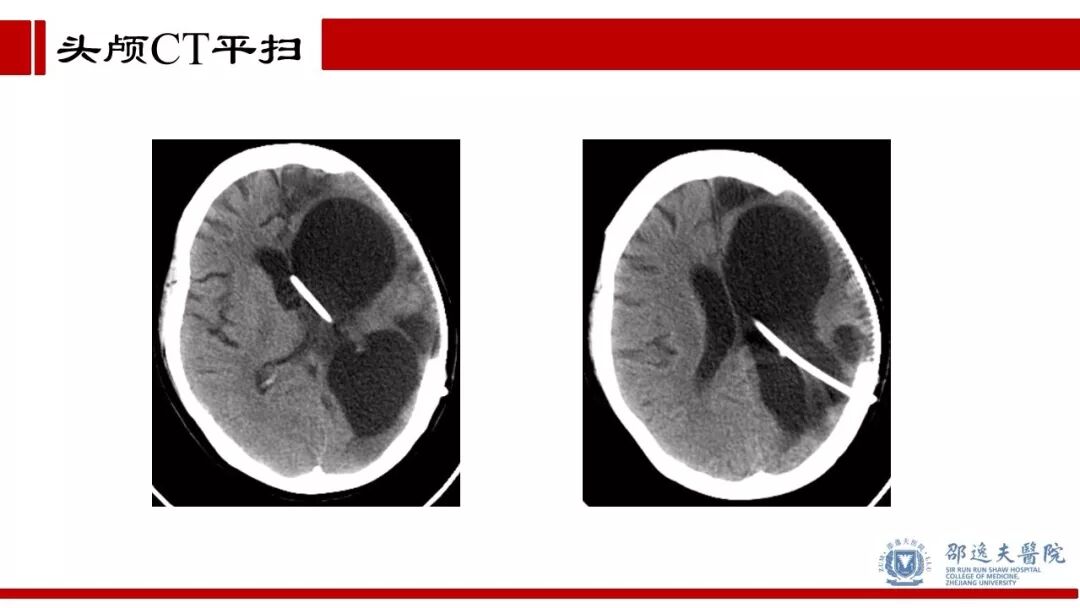

王义荣主任团队:脑室心房分流术病例分享

今天为大家分享的是《贝朗时间》第四十八期,浙江大学医学院附属邵逸夫医院神经外科王义荣主任团队带来的:脑室心房分流术病例分享,欢迎阅读、分享!